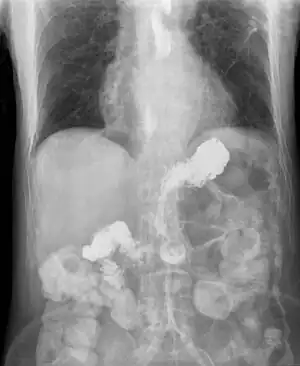

![]() | |

| X-ray showing radiocontrast from the stomach (white material below diaphragm) entering the esophagus (three vertical collections of white material in the mid-line of the chest) due to severe reflux | |